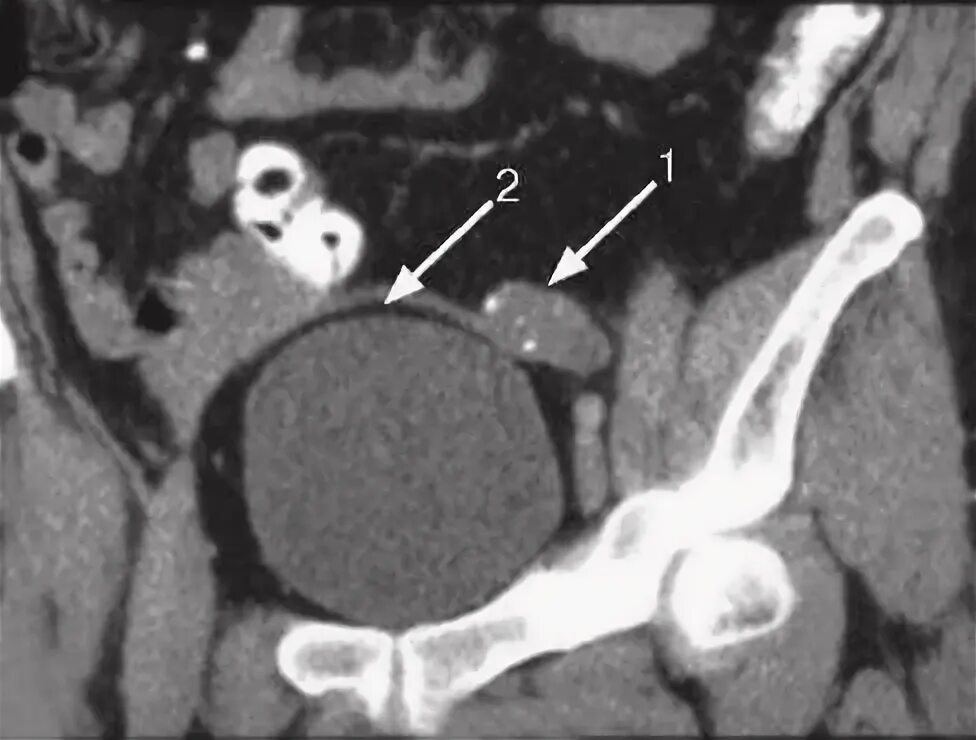

Аномалия полов орган